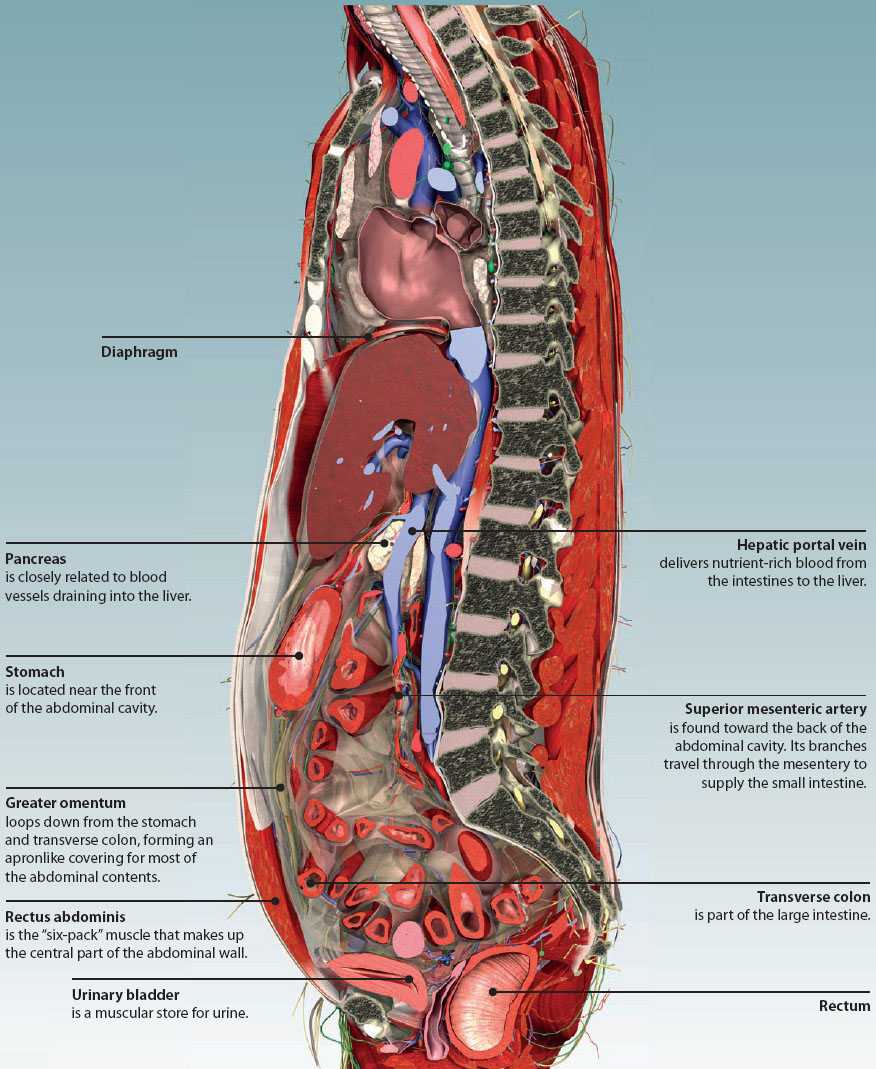

completeanatomy.cnabdomen regions realistic gross spine unveiled reveals

completeanatomy.cnabdomen regions realistic gross spine unveiled reveals

guidelibmisjoinder.z22.web.core.windows.netUnderstanding Abdominal Divisions | Anatomy Snippets | Complete Anatomy

guidelibmisjoinder.z22.web.core.windows.netUnderstanding Abdominal Divisions | Anatomy Snippets | Complete Anatomy

completeanatomy.cnAbdomen (Human Anatomy) - Image, Definition, Function, Diseases And More

completeanatomy.cnAbdomen (Human Anatomy) - Image, Definition, Function, Diseases And More